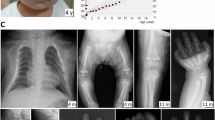

Pseudohypoparathyroidism Ia (PHP-Ia), is an inherited disease with clinical hypoparathyroidism caused by parathyroid hormone resistance (PTH), and shows the phenotype of Albright hereditary osteodystrophy (AHO), including short stature, obesity, round face, brachydactyly, and subcutaneous ossification. This disease is caused by mutation that inactivates the α-subunit of Gs, the stimulatory regulator of adenylyl cyclase. Here, a novel frameshift mutation (delG at codon 88) in exon 4, and a missense mutation (R231H) in exon 9 of the Gsα gene were identified in two Japanese patients with sporadic PHP-Ia. Deletion of a G in exon 4 at codon 88 in the first patient produced a premature stop codon, resulting in the truncated protein. The second patient had a previously reported R231H mutation. Because this amino acid is located in a region, switch 2, that is thought to interact with the βγ subunit of Gsα protein, this mutation may impair Gs protein function. We report here one novel Gsα mutation, and note that mutations in Japanese patients with PHP-Ia are probably heterogeneous.